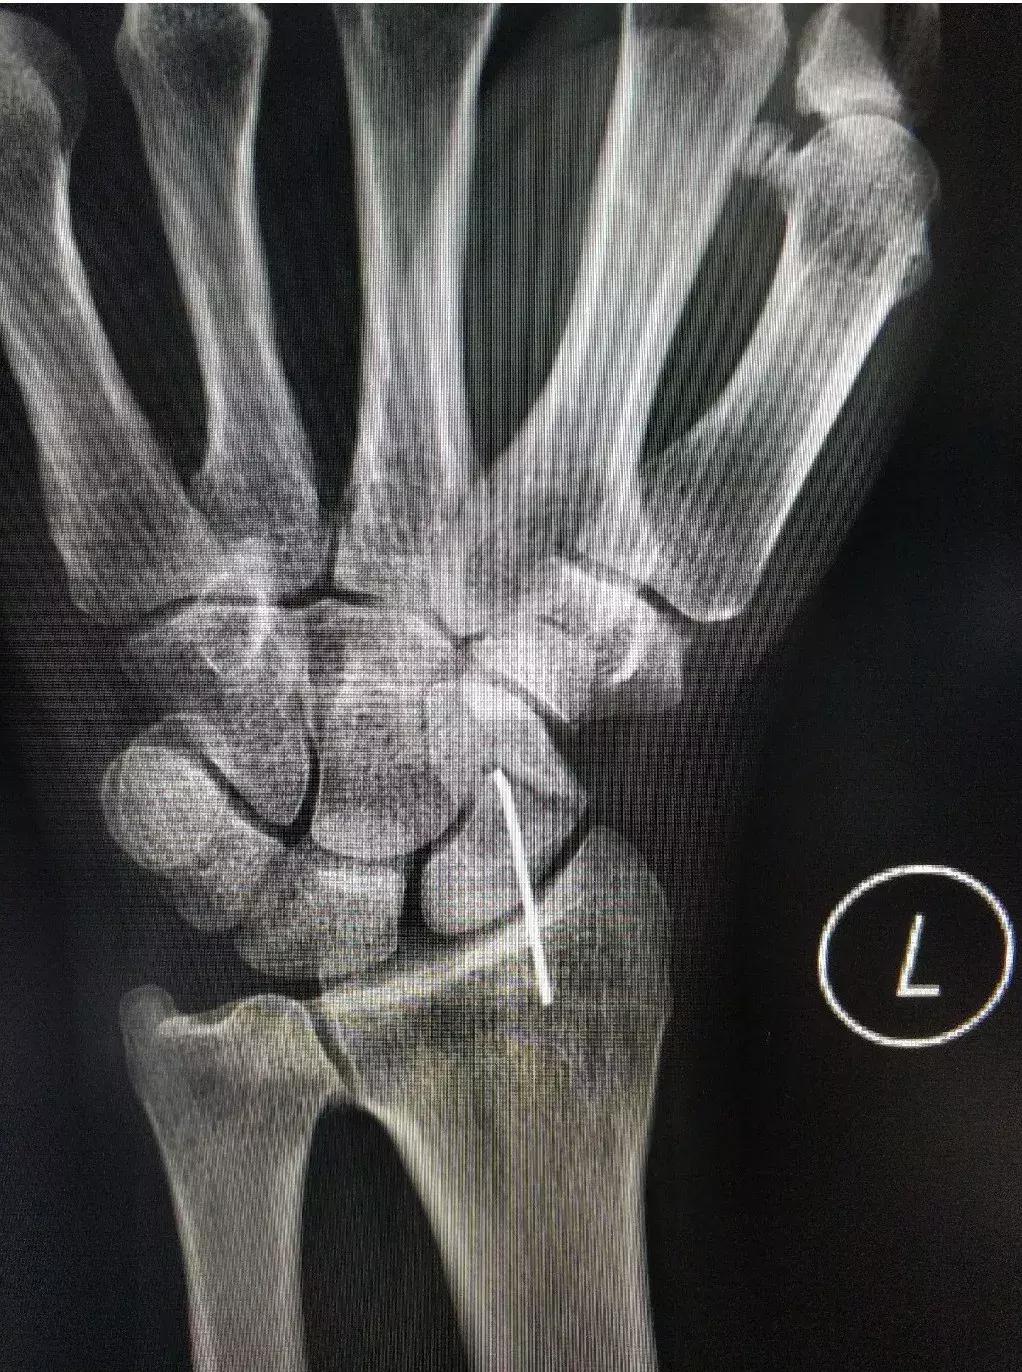

1、影像学定位:由骨科李志强主治医师完成精准定位

2、冲击波治疗:针对该患者骨折情况,由康复医学科郑闵琴教授实施操作。应用高能冲击波作用于骨不连处,处理骨折两端硬化的骨质,造成其两硬化端粉碎性微骨折,出现血肿形成.随之无菌性炎症产生,炎性反应和炎性细胞的释放产物可以产生各种成骨诱导因子而募集骨祖细胞诱导成骨。